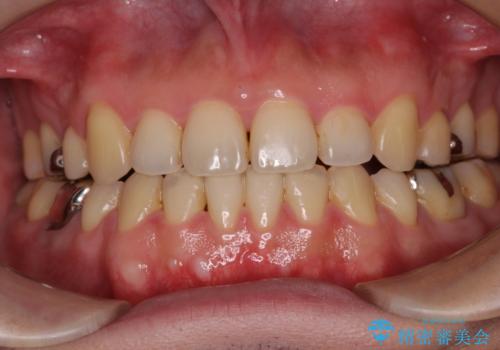

インビザラインの特性を活用して奥歯の咬み合わせを圧下させることで、前歯のオープンバイトを改善さえることができました。

- 1年4ヶ月

- 5-10回